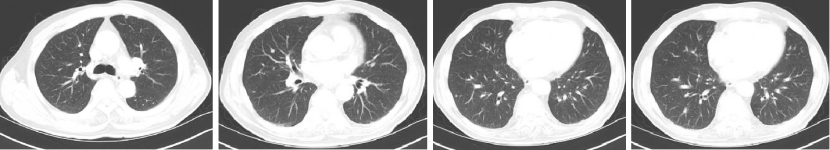

Q1 对于晚期转移性结直肠癌患者,目前,免疫治疗在新辅助治疗中的研究进展和临床应用如何? 结直肠癌是全球第三大肿瘤,转移性结直肠癌的5年生存率只有14%,治疗手段包括手术、化疗、放疗和靶向治疗等。免疫检查点抑制剂的出现也改写诊疗指南。大肠癌dMMR/MSI-H亚型约占所有病例的15%和mCRC病例的5%。由于dMMR/MSI-H的高突变率,肿瘤具有高免疫原性,使其能够激活免疫系统的抗肿瘤作用。 KEYNOTE-177这是一项三期国际开放标签随机对照研究,入选MSI-H/dMMR的IV期结直肠癌患者,比较帕博利珠单抗治疗(200 mg,每3周1次,最多35个周期)与在一线中使用或不使用抗VEGF或抗EGFR单克隆抗体的标准双药化疗,主要终点是PFS和OS。结果显示,帕博利珠单抗组患者的中位PFS时间为16.5个月 VS 8.2个月;3年PFS率分别为42% VS 11%,3年OS率分别为61% VS 50%。帕博利珠单抗组ORR为45.1%(20例完全缓解,49例部分缓解),化疗组为33.1%(6例完全缓解,45例部分缓解);帕博利珠单抗组83.5%的患者至少维持缓解了2年;在化疗组中,只有33.6%的患者缓解持续时间≥2年。KEYNOTE-177研究证实了帕博利珠单抗可以作为MSI-H或dMMR患者的一线标准治疗。 在2021版CSCO结直肠癌诊疗指南中,MSI-H结直肠癌姑息一至三线均推荐免疫治疗,其中帕博利珠单抗作为一线治疗的一级推荐;CheckMate-142研究选择MSI-H/dMMR转移性结直肠癌患者,单免后线vs双免后线vs 双免一线:ORR 39% vs 65% vs 71%,DCR 69% vs 81% vs 84%,一线双免完全缓解率为13%。结果说明双免好于单免,一线好于后线。CheckMate-142研究具有划时代意义,它将免疫治疗从后线前移到一线。 COMMIT研究是一项前瞻随机开放标签的三期临床研究,评估了阿特珠单抗单药治疗对比mFOLFOX6(氟尿嘧啶、奥沙利铂、亚叶酸钙)+贝伐珠单抗+阿特珠单抗一线治疗dMMR或MSI-H转移性结直肠癌的疗效和安全性,目前该试验还在进行中。未来该项研究的结果将回答对于MSI-H晚期结直肠癌,在一线免疫治疗的基础上联合化疗和抗血管靶向药物是否可以进一步提高免疫治疗的疗效。 CheckMate 8HW是另一项随机对照三期临床研究,在一线治疗dMMR或MSI-H转移性结直肠癌中,比较纳武利尤单抗单药、纳武利尤单抗联合伊匹木单抗以及研究者选择的化疗这3种方案的疗效。这项研究将头对头地比较对于MSI-H晚期结直肠癌双免联合是否优于单免的疗效。 Q2 对于MSI-H/dMMR型局部晚期结直肠癌(LACRC),新辅助免疫治疗探索的进展与应用前景如何?有哪些潜在预测疗效的生物标志物? 对于MSI-H/dMMR型局部晚期结直肠癌患者,新辅助免疫治疗可以在肿瘤手术前,提前使患者的免疫系统识别肿瘤细胞,从而使患者的免疫系统更好地产生免疫应答。目前结直肠癌新辅助治疗的探索均为二期研究,探索模式多为双免疫或免疫联合化疗方案,直肠癌多为免疫联合放化疗(同步或序贯)的模式。 NICHE研究是探索纳武利尤单抗联合伊匹木单抗用于Ⅰ-Ⅲ期结肠癌新辅助治疗的二期临床研究,研究共纳入40例结肠癌患者,其中21例为dMMR,20例为pMMR(1例患者同时为pMMR和dMMR),81%的dMMR患者和40%的pMMR患者为临床Ⅲ期结肠癌。患者在接受首次免疫治疗后不迟于6周内接受结肠癌手术,dMMR结肠癌缓解率100%,其中完全缓解的患者占60%,MPR为95%;pMMR治疗组27%的患者也对免疫治疗产生了良好的应答。 NICHE2研究,纳入更多患者,探寻非转移性dMMR结直肠癌患者双免治疗(伊匹木单抗+纳武利尤单抗)的疗效,主要终点为安全性,3年无病生存期。结果显示:MPR率95%,PCR率67%,中位随访13.1个月后没有患者出现疾病复发,毒性可耐受。 NCT04165772研究(前瞻性,单臂,Ⅱ期研究),Ⅱ期和Ⅲ期患者接受新辅助dostarlimab(多塔利单抗)共6个月,结果显示CCR率为100%。 PICC研究是特瑞普利单抗联合或不联合塞莱昔布新辅助治疗错配修复蛋白缺陷或微卫星高度不稳定的局部进展期结直肠癌的双臂随机Ⅱ期临床试验,结果显示完全缓解率高达88%,进一步表明dMMR结直肠癌免疫疗效惊人,潜在替代放化疗及手术。 对于MSI-H或dMMR结直肠癌,NCCN结直肠癌指南中,新辅助治疗增加纳武利尤单抗±伊匹木单抗或帕博利珠单抗单药方案;转化治疗可以选择双免疫或单免疫用药方案。 但并非所有患者都能从免疫治疗中获益,故筛选免疫治疗的疗效预测生物标志物将显得尤为重要。近年来研究主要集中在包括MSI-H、PD-L1过表达、TMB-H(TPS3645)、POLE或POLD1基因突变、PI3K/AKT/mTOR通路、新抗原(身份和数量)、免疫系统状态(免疫细胞特征、T细胞受体相关)等。 Q3 您如何看待对于临床中MSI-H/dMMR 转移性结直肠癌患者使用免疫治疗,部分患者仍然会出现耐药问题? Q4 晚期结直肠癌通常预后相对较差、患者生存期不长,依然是我国困扰结直肠肿瘤治疗的瓶颈问题,但有治愈的可能,此时临床医生制定正确合理用药方案尤为重要。今年上半年发布的CACA-RC指南推荐不适合强烈治疗患者应用曲氟尿苷替匹嘧啶片(TAS-102)联合贝伐珠单抗,作为晚期不可切除结直肠癌姑息一线治疗方案。请您谈谈该推荐治疗对我国晚期不可切除结直肠癌患者的临床治疗带来怎样的获益? 今年上半年CACA-RC指南推荐了不适合强烈治疗的患者应用TAS-102联合贝伐珠单抗作为不可切结直肠癌一线治疗方案,是在不可切除晚期结直肠癌一线治疗中石破天惊的一项突破。晚期mCRC的标准化疗方案在指南中是以奥沙利铂或伊立替康为基础的FOLFOX和FOLFIRI方案,在此基础上,可以根据基因分型联合西妥昔单抗或者贝伐珠单抗,但是依旧有部分患者身体状况无法耐受加强化疗,针对这一类患者的治疗方案选择非常有限,且预后情况并不理想。TAS-102+贝伐珠单抗治疗方案毒副反应相对较低,(临床试验提示比贝伐珠单抗联合卡培他滨效果好)疗效确切,在未来较长一段时间内,尤其是目前疫情肆虐,患者不方便住院治疗时,TAS-102可作为国内不适合强烈治疗的mCRC患者及老年患者的一线治疗优选方案,并为患者带来持续的、更优的生存获益。 二 病例分享 专家简介 王峰 教授 医学博士,副主任医师,硕士研究生导师 滨州医学院附属医院肿瘤科副主任 澳大利亚悉尼维斯迈医学中心访问学者 中华医学会放射肿瘤治疗学分会骨与软组织学组委员 中国临床肿瘤学会(CSCO)神经系统肿瘤专家委员会委员 山东省医师协会肿瘤精准医疗医师分会常务委员 山东省医师协会肿瘤放疗医师分会委员 山东省抗癌协会消化道肿瘤分会常务委员 山东省医学会咽喉肿瘤多学科联合委员会委员 山东省医学会烟草病学与戒烟多学科联合委员会委员 山东省健康管理协会消化道肿瘤防治分会常务委员 山东省医学会放射肿瘤学分会青年委员 山东省医学会妇科肿瘤多学科联合委员会委员 滨州市医学会放射肿瘤学专业委员会副主任委员 01 基本情况 (一)基本信息 患者男性,65岁,于2021-08-26第一次入滨州医学院附属医院风湿免疫科。 主诉:发作性右踝关节肿痛3年,再发1月。 查体:双足第一跖趾关节可见红肿,伴局部皮温升高。 既往史、个人史:既往脑梗死病史7年余,未遗留后遗症;有“膀胱结石”病史1年余,未系统诊治;有“痛风性关节炎”3年余,曾于滨州医学院附属医院风湿免疫科治疗。有高血压病史10年余,最高血压180/110mmHg,口服“吲达帕胺片”,血压控制可。 常规检查发现2次大便潜血阳性。 (二)辅助检查结果 1.肠镜检查 直肠、乙状结肠:直肠距肛门7cm可见一巨大溃疡型病变,表面溃烂,污秽苔,周边环堤样隆起,累及管腔1/3周圈,管腔无狭窄,于病变周边多点活检8块,质脆易出血;乙状结肠见一0.5cm*0.3cm息肉,余黏膜光滑,皱襞清晰,蠕动规律;肛管未见异常。降结肠、横结肠:横结肠见一0.3cm*0.4cm 0-IIa型息肉,表面粗糙,余黏膜光滑,血管纹理清晰,未见异常。 诊断:1.直肠Ca(进展期 溃疡型);2.结肠多发息肉——内镜下冷切除术+息肉摘除术。 2.胸部、上腹部未见明显异常。 直肠MR增强+DWI:直肠距肛缘约5.5cm处肠壁明显不均匀增厚,累及长度约6.0cm,呈等/长T1、等/稍长T2信号,T2压脂呈不均匀高信号,DWI呈高信号,ADC图信号减低,增强扫描呈明显不均匀强化,相应局部管腔狭窄,邻近浆膜面模糊,周缘可见小淋巴结。 02 治疗经过 2021-09-08:于全麻下行全直肠系膜切除+末端回肠预防造瘘术。 术中见:肝脏、胃、腹壁等无转移性结节。肿块位于腹膜返折处,活动度差,侵及浆膜。肠周见明显散在肿大淋巴结。 术后病理:直肠下段中分化腺癌,侵犯外膜下脂肪组织,肿瘤出芽分级(高级别,Bd3),侵犯神经侵犯,未见确切脉管内癌栓;两侧手术切缘、环周切缘及标记切缘内均未查见癌累及,肠周淋巴结内未查见转移癌(0/17)。pTNM分期:pT3N0Mx。免疫组化结果:CK(+),MSH2(+),MSH6(+),MLH1(+),PMS2(+),MDR-1(3+),HER2(3+),P53(3+),Ki-67阳性率约70%。 术后诊断: 1.直肠癌II(pT3NOMO)期术后; 2.结肠多发息肉术后; 3.痛风性关节炎; 4.高血压病(3级 很高危); 5.脑梗死。 CSCO指南: 2021-10-04至2022-06-03:FOLFOX方案化疗10周期(奥沙利铂150mg d1+氟尿嘧啶 0.7g d1+4.4g civ);术后预防性放射治疗DT5000cGy/25f,同步卡培他滨。 2021-11-25至2021-12-06:尿培养提示肺炎克雷伯菌感染,结合泌尿外科、感染科会诊意见,给予左氧氟沙星抗感染治疗。 2022-06-12 肺无法穿刺活检。 基因检测示:(直肠)KRAS/BRAF/NRAS/PIK3CA 基因均未检出突变。伊立替康UGT1A1基因检测结果:非风险基因型。 CSCO指南: 2022-06-20:西妥昔单抗联合FOLFIRI方案治疗(西妥昔单抗900mg d1,伊立替康320mg d1,氟尿嘧啶0.7g iv 4.3g civ)。 2022-07-06:骨髓抑制、腹泻,西妥昔单抗联合FOLFIRI方案治疗(西妥昔单抗900mg d1,伊立替康280mg d1,氟尿嘧啶0.7g iv 4.3g civ)。 疗效对比: 循证依据: C-TASK FORCE研究:首个证实TAS-102联合贝伐珠单抗治疗mCRC的疗效及安全性研究。TAS-102联合贝伐珠单抗是难治性mCRC患者潜在治疗选择,更多临床获益有待进一步研究。 TAS-102联合贝伐珠单抗治疗mPFS时间和mOS时间分别为5.6个月和11.2个月。 TAS-102联合贝伐珠单抗不良反应主要为血液学毒性。 日本大样本RWS:TAS-102和瑞戈非尼不同排序的回顾性研究。 日本大样本RWS:TAS-102单药较瑞戈非尼单药,可显著延长mOS,降低AE。 日本大样本RWS:两药序贯疗效优于单药,且≥65岁先用TAS-102获益更显著。 日本大样本RWS:TAS-102序贯瑞戈非尼组持续治疗时间更长。 2022-07-27至今 给予贝伐珠单抗联合TAS-102治疗期间复查CT评估SD,胃肠道反应不重,骨髓抑制Ⅰ度,耐受性尚可。 *本文仅代表专家观点,并经专家审校。